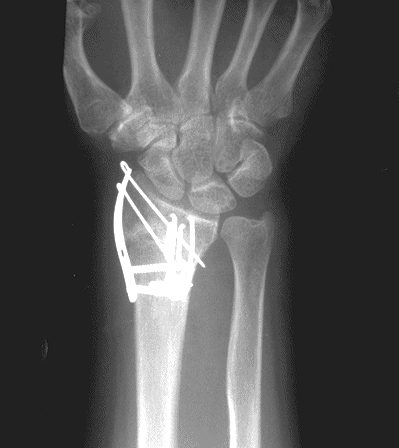

Case 2 Postop